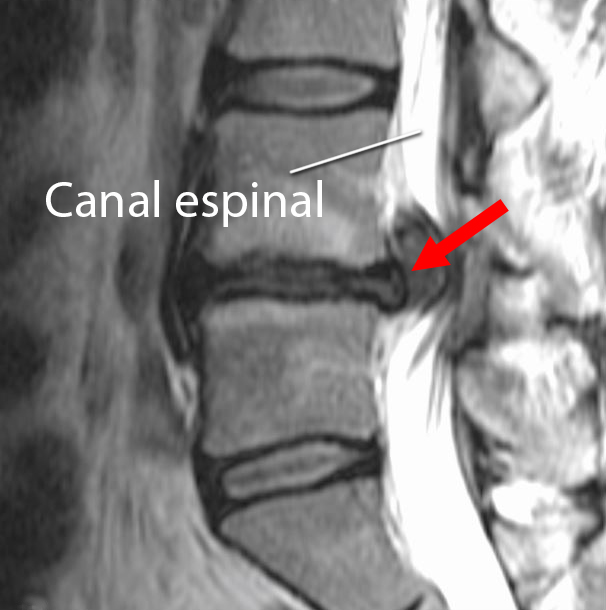

Exploraciones de imágenes por resonancia magnética (Magnetic resonance imaging, MRI). Con las exploraciones de MRI se pueden obtener imágenes claras de los tejidos blandos del cuerpo, incluidos los discos intervertebrales. Su médico puede indicarle una MRI para confirmar el diagnóstico y obtener más información sobre qué nervios espinales están afectados.

La exploración de MRI muestra una hernia de disco en la zona lumbar (flecha). El disco se hincha hacia el canal espinal, ejerciendo una presión en columna vertebral y las raíces nerviosas.

Reproducido de Truumees E, Prather H (eds): Orthopaedic Knowledge Update 5. Rosemont, IL. American Academy of Orthopaedic Surgeons, 2017, págs. 243-251.